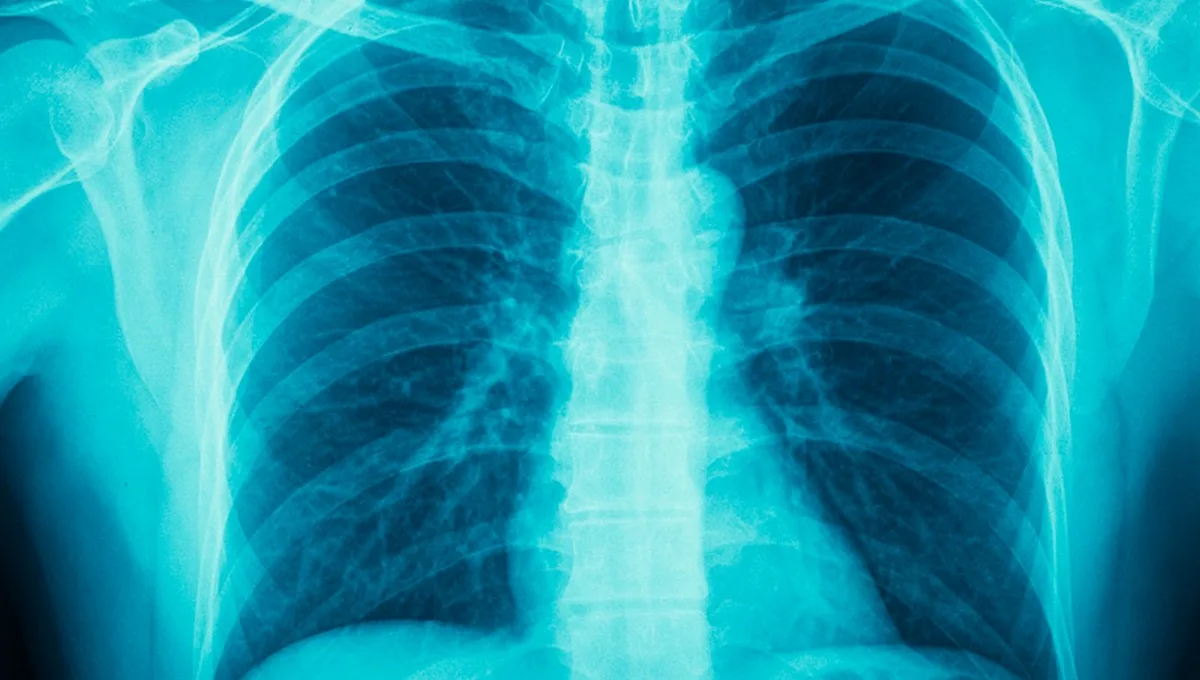

Что делать, если при кашле заметили кровь?

• рентген;